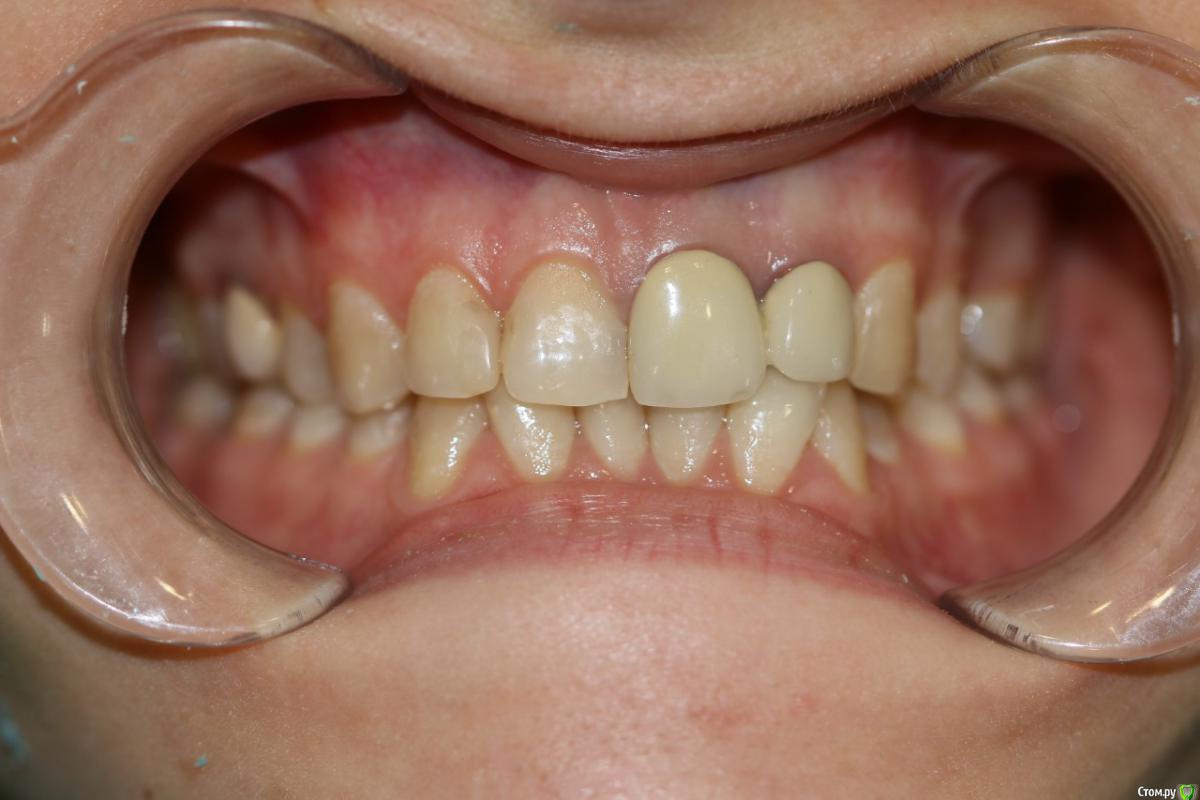

В декабре 2019 г мне поставили коронки emax. И на соседние 2 зуба- виниры (чтоб смотрелось норм)

Результат постановки коронок меня не устроил. Зубы поставлены как будто под наклоном и между коронками в одном месте появился огромный десновой сосочек, который мешает жить, при разговоре и слюна вылетает и свистеть можно) врач уверяла, что зарастёт за 2 недели. Но прошло 3 месяца, ситуация не изменилась.

Я обратилась к другим ортопедам за советом, может мне поставили коронки не так как надо? Почему щель? И большинство ответов было таким- коронка одна поставлена не плотно. И вообще чтобы поставить качественно коронки , нужна ортодонтия.

У вас есть скривление зубных дуг в разных плоскостях, для правильного функционирования, необходимо провести анализ окклюзионных взаимоотношений чтобы принять решение на сколько вам необходима ортодонтическая подготовка, и сделать прицельные снимки в области установленных керамических конструкций, что бы понять в чем причина ваших беспокойств, на фото я не вижу огромного десневого сосочка.